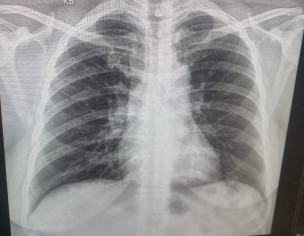

Asking for Mother, Female, 43 years old, Karachi

My mom is 43 years old and she’s had Covid since a week. Her symptoms now are much better AH but she still has troubled breathing and cough with sputum . Doctor suggested to get a chest X-ray so here’s her chest X-ray. Can you please tell is there any problem?

x ray is normal but can get an online appointment for a detailed discussion of symptoms

Alhamdolillah her xray ok plz share her oxvgen saturation and Cbc